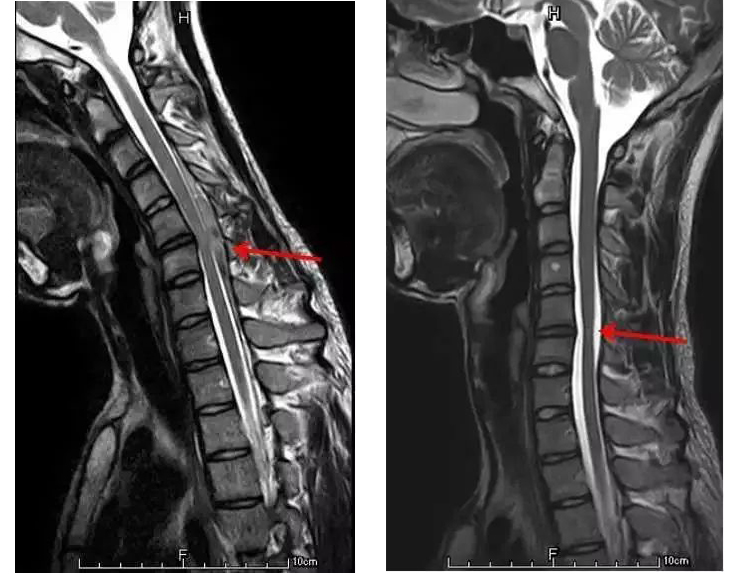

平山病的发病机制和病因目前尚无定论,多认为是因为在生长发育高峰期,青少年的脊髓、脊柱、神经根等结构生长速度不匹配,导致患者颈椎屈曲时,脊髓及神经根等重要结构受到压迫或缺血性损伤,从而引发相应的肌肉萎缩。因此,平山病的诊断需要应用特殊的颈部自然位和屈曲位磁共振(MRI)以及规范、多方面的肌电图检测。

颈部自然位MRI